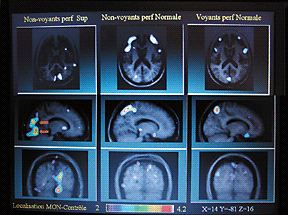

La colonne de gauche représente le cerveau de non-voyants qui ont obtenu une performance supérieure aux voyants (colonne de droite) en localisation auditive et à d'autres non-voyants (colonne du milieu). L'oeil averti observera en effet que les cerveaux de la première colonne présentent des activations des aires occipitales. |

À son tour, Frédéric Gougoux a désiré pousser ces résultats un peu plus loin. Grâce à la tomographie par émission de positrons, mieux connue sous l'appellation anglaise PET-Scan, il a voulu aller voir plus précisément ce qui se passait dans le cerveau des non-voyants au moment de la localisation sonore. Franco Lepore, professeur au Département de psychologie et directeur du CERNEC, ainsi que Robert Zatorre, professeur à l'Institut de neurologie de l'Université McGill, ont accepté de diriger ses travaux. Maryse Lassonde, professeure au même département, a aussi accepté de collaborer aux travaux de l'étudiant.

L'équipe s'est ensuite déplacée à l'Institut de neurologie, plus précisément au Centre d'imagerie cérébrale McConnell. «Nous avons intégré une couronne de haut-parleurs dans le tube d'un scanner, précise l'étudiant. Les sujets, dont la tête était immobilisée dans le tube, tenaient dans leur main une manette de jeu vidéo. Ils devaient indiquer d'où venait le son entendu à l'intérieur de la machine avec la manette.» Grâce au PET-Scan, le jeune chercheur et son équipe ont constaté qu'au cours de l'exercice, chez les sujets les plus performants, un débit sanguin cérébral important était dirigé vers la zone occipitale du cerveau. «Nous avons réussi à cibler de façon précise les régions cérébrales activées chez les non-voyants, poursuit-il. Comme nous l'avions anticipé, certaines de ces zones sont normalement associées à la vision.»

Victoire supplémentaire: M. Gougoux a constaté que le débit sanguin cérébral irriguant la zone occipitale des sujets non voyants était directement proportionnel à leur performance. Autrement dit, plus le sujet avait de facilité à repérer les sources sonores, plus sa zone occipitale était active. «Ceci vient confirmer les hypothèses que nous avions émises jusqu'à maintenant», se réjouit-il.